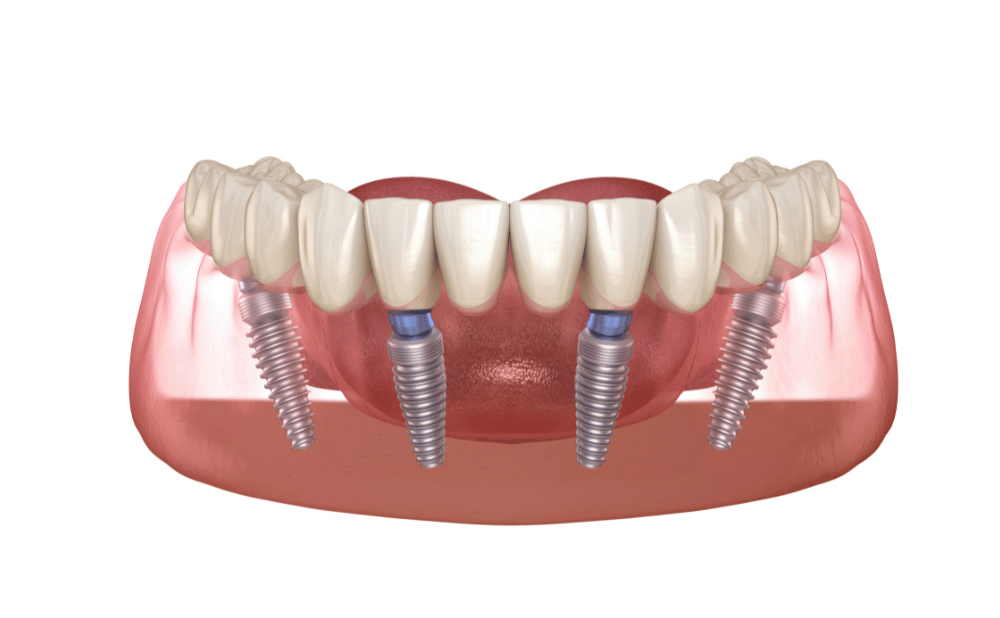

オールオンフォー・ザイゴマインプラント

骨吸収や極端な骨不足がある場合は、オールオンフォーやザイゴマインプラントといった、高度治療が有用です。

また、骨移植を避けて短期間で回復が可能なケースもあります。

オールオンフォーは片顎250万円~450万円、ザイゴマインプラントは片顎400万円~600万円ほどが相場です。